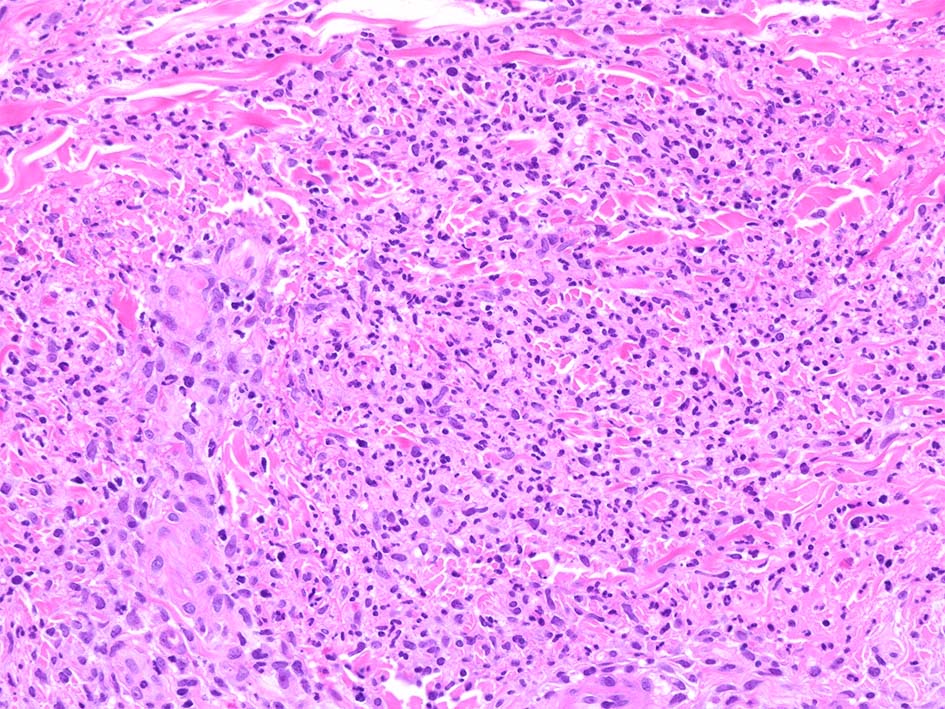

病理所見

典型疹は真皮の好中球浸潤より始まる. 病初期では, 好中球浸潤は表皮に及ばない. 病期が進むにつれ, 2次的好中球浸潤が認められるようになる.

真皮上中層で広範囲に好中球が密に浸潤する所見がSweet病の最大の特徴. 好中球活性が亢進し, apoptosisを起こして核塵(核破砕物)がみられることが多い. 浸潤が顕著になると真皮上中層が浮腫をきたして, 皮疹が隆起する.

真皮上層浮腫がつよくなり表皮下水疱を形成することがある. 水疱内にはフィブリンや炎症細胞が多数認められる.

真皮の好中球浸潤部には毛細血管, 細動静脈が巻き込まれるが, 血管のフィブリノイド壊死は認められない.(鑑別が難しいことのあるBehçet病では2012年より, 壊死性血管炎があるとされており鑑別のための病理所見となっている)

Case02 前胸部皮膚

73 year old male

lt

骨髄異形成症候群で入院中. 発熱, 関節痛に加えて四肢, 胸部など上半身に潰瘍形成をともなう浮腫性紅斑が出現してきた. 皮下硬結あり. Sweet症候群と診断.

中央に黒色痂皮を示す紅斑. 硬結の強い部位から生検される.

HE x40. 表皮下水疱あり. 真皮上層は浮腫状. 真皮から皮下組織にかけて, 多数の好中球が浸潤している. リンパ球, 好酸球が混在, 核破砕物を貪食するマクロファージが増加. 膠原線維にはところどころ変性が見られる.

真皮上層には核破砕物が多く, 好中球浸潤が認められる. 慢性炎症性細胞も浸潤している.

フィブリノイド壊死を呈する血管炎は認められない.

皮下脂肪織炎病変には局所的なhemophagocytosisが認められる. 血管にはfibrinoid necrosisは見られない。